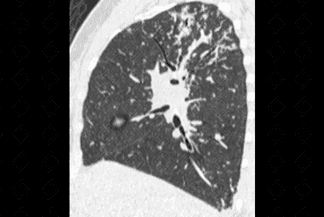

Texto alternativo para a imagem Figuras 1, 2, 3, 4 e 5. Créditos: Dra. Elazir Mota - Rio de Janeiro/RJ

Descrição das figuras 1, 2, 3, 4 e 5: Tomografia computadorizada do tórax com cortes axiais evidenciando pequenos nódulos distribuídos principalmente ao longo dos brônquios e vasos pulmonares (setas vermelhas). Nos cortes coronal e sagital observa-se o predomínio das anormalidades descritas nas regiões superiores e médias, de localização mais central.

• As alterações pulmonares predominam nas regiões centrais e lobos superiores, sendo geralmente bilaterais e simétricas. Predominam os pequenos nódulos sólidos com distribuição perilinfática, ou seja, ao longo dos brônquios, septos interlobulares, vasos pulmonares e regiões subpleurais. Lesões nodulares escavadas e derrame pleural são raros na doença;